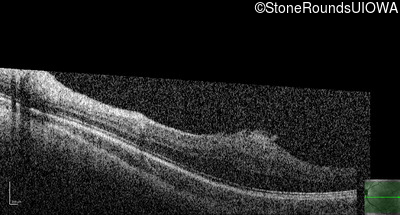

This 9 year old male was noted to have some crossing of his eyes at 2 months of age and the eye exam which followed identified a retinal lesion in the right eye. When he was six years old an epiretinal membrane was noted in his left eye. Two years later it was decided that it was a thin hamartoma in that eye as well. He underwent neuroimaging at age 7 which identified bilateral acoustic neuromas.

| Age at visit: 8 years |

| Age at visit: 10 years |

| Age at visit: 11 years |

| Age at visit: 14 years |